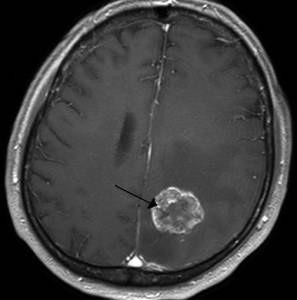

Злокачественная опухоль

Описание

Злокачественная опухоль представляет собой патологическое новообразование, опасное для жизни, состоящее из раковых клеток, способных к быстрому росту и метастазированию.

Тип боли

Интенсивность и характер боли зависят от локализации опухоли, стадии заболевания и индивидуальных особенностей пациента.

Другие проявления

На ранних стадиях опухоль может не проявляться, пока не начнется интенсивный рост. В этот момент состояние пациента ухудшается, могут возникать тошнота, утомляемость, рвота, нарушения слуха и зрения, трудности в распознавании речи, а также расстройства общей и мелкой моторики.

Клиническая картина рака разнообразна и многогранна.

Методы диагностики и терапии

Диагностика включает комплексные исследования: КТ, МРТ, рентген, лабораторные анализы, гистологию и цитологию. Лечение обычно хирургическое, с возможным назначением курса химиотерапии или лучевой терапии, а затем длительного поддерживающего медикаментозного лечения.